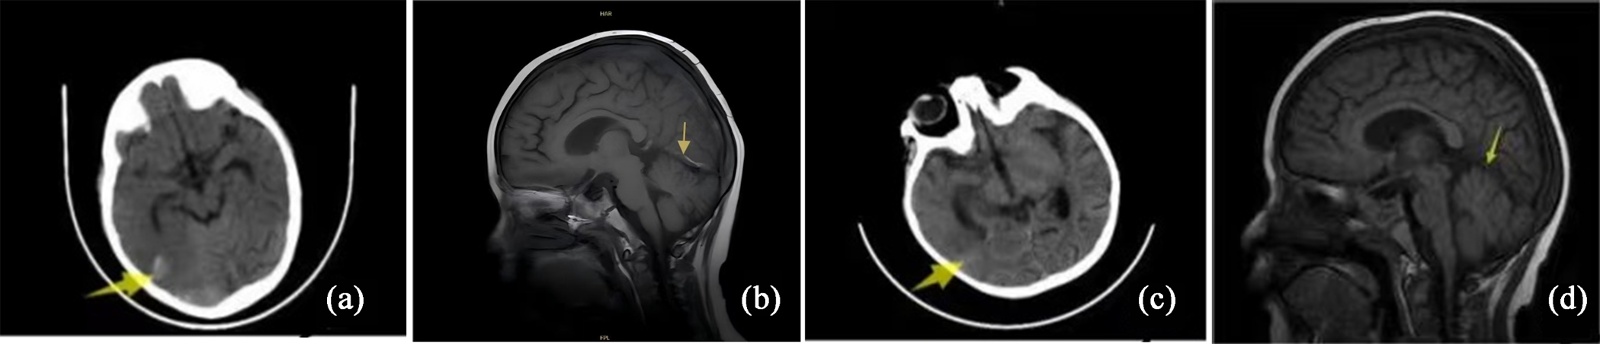

患者,女,3岁。因“发热伴血象异常1月余”入院。依据骨髓MICM结果诊为急性淋巴细胞白血病(B系,中危)。入院时患儿颅脑MR未见异常,血凝常规正常。按照CCCG-ALL-2020方案给予VDLD诱导缓解治疗。治疗期间多次血凝常规示FIB最低0.51 g/L,AT-III最低55.8%,余未见异常,予输注人纤维蛋白原后FIB正常。治疗第33天患儿出现抽搐,表现为全身抽搐继发右侧肢体局部抽搐,血常规、电解质检测无异常,血凝常规:PT 14.6 s,APTT 36.3 s,FIB 1.43 g/L,AT-III 50%,DD 260 ng/mL。颅脑CT示右额顶叶交界区、右颞枕叶交界区血肿破入蛛网膜下腔可能性大(如图3(a))。脑MR示右横窦、乙状窦血栓并右顶叶、颞叶皮层区出血可能(如图3(b))。予输注冷沉淀及对症治疗,抽搐发作第4天加用低分子肝素钠抗凝,治疗1周复查颅脑CT示脑出血吸收(如图3(c));脑MRV示上矢状窦、双侧大脑大静脉、内静脉、右侧横窦、乙状窦、颈内静脉管腔显影差。低分子肝素钠治疗45天后改为利伐沙班口服2月。后续均未再应用PEG-Asp。抗凝治疗3个半月复查颅脑MR较前好转(如图3(d)),停用利伐沙班。抗凝治疗期间动态监测血凝正常。

(a) 治疗前脑CT;(b) 治疗前脑MR;(c) 治疗后脑CT;(d) 治疗3.5月后脑MR。

Figure 3. Comparative cranial imaging of case 3: Pre-treatment vs post-treatment

3. 病例3治疗前后颅脑影像变化